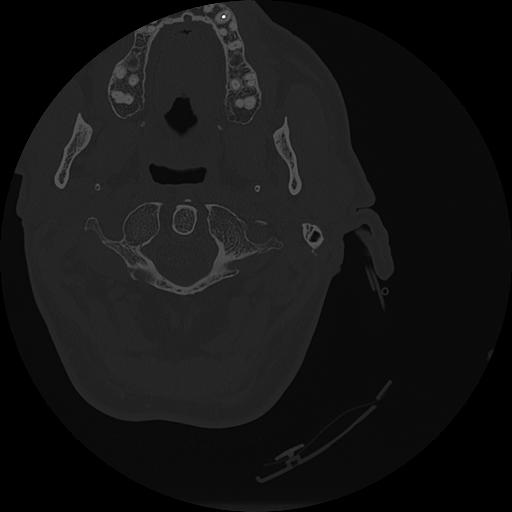

7 HUESO,,Vol,0.5,HUESO,,